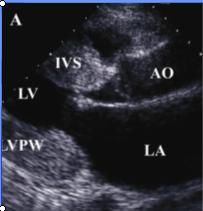

3.超聲心動圖:心尖四腔可見心臟增大而以左心室擴大為顯著,左室室壁運動瀰漫性減弱;如有附壁血栓則多發生在左室心尖部;多合併有二尖瓣和三尖瓣反流。測定射血分數和左室內徑縮短率可反映心室收縮功能。室壁運動節段性異常需要與缺血性心肌病鑑別,將超聲心動圖檢查與多巴酚丁胺負荷實驗相結合有助於鑑別。下圖為擴張型心肌病的三維超聲心動圖圖像。4.冠脈造影檢查:存在胸痛的DCM患者需要作冠脈造影或冠脈CTA檢測,有助於與冠心病鑑別。左心室造影提示心室腔擴大,可見整體性的室壁運動減弱。

超聲心動圖在本病早期即可見到心腔輕度擴大,尤其左心室,室壁運動減弱,後期各心腔均擴大,室間隔與左室後壁運動也減弱。二尖瓣前葉雙峰可消失而前後葉呈異向活動。左室噴血比數常減至50%以下,心肌縮短比數也減小。可能有少量心包積液。